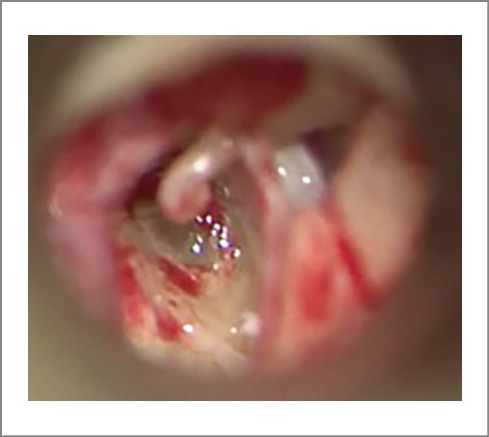

In March 2023, patient L., 24 years old, presented at the St. Petersburg Research Institute of ENT with hearing loss in both ears, more on the left, and periodic mixed tinnitus. She had these symptoms for 2 years. According to the patient, she had no previous history of chronic or acute ear diseases; her family history is unremarkable. From 2010 to 2016, she was followed up by an epileptologist for an epilepsy episode; in 2016, she was withdrawn from the follow-up. Somatically, she had an arach-noid retrocerebellar cyst and a congenital anomaly of the urinary system, left kidney duplication. Other findings were unremarkable. The otoscopic pattern was normal. When conducting acoustic impedance measurement, the type A tympanogram on both sides was recorded; the stapedial reflex-es on both sides were absent. Tonal audiometry corresponded to a grade 2 mixed hearing loss on the left, with the Carhart notch at 2000 Hz and grade 1 conductive hearing loss on the right (Fig. 1). When examined with a 128 Hz tuning fork, the lateralization of sound in the Weber test spread to the left ear, the Rinne’s, Federicci’s and Gellé tests were negative on both sides. CT (Fig. 2, 3) and virtual CT endoscopy of the ME (Fig. 4) showed no changes in the ME and IE. The configuration of the semicircular canals, the vestibular aqueduct, and the perilymphatic duct were unremarkable. TB CT showed no demineralization of the labyrinth bone capsule, gross deformations of the AO chain, or abnormalities in the structure of the ME and IE.

Fig. 3. MSCT scans of the left TB showed the normal structures of the IE and ME: a – normal dimensions and absence of the bone capsule defects in the posterior semicircular canal; b – normal dimensions and absence of bone capsule defects in the lateral semi-circular canal; c – normal dimensions and absence of bone capsule defects in the superior semicircular canal; d – normal dimen-sions and absence of defects in the IAC wall.